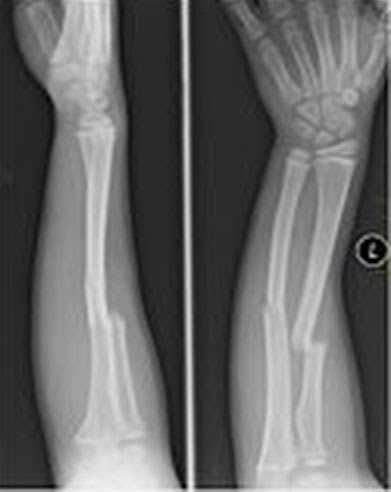

That compound, calcium phosphate, has been known to help drive stem cells to become bone, but no one knew why or how. So, getting the desired impact has been an inefficient and expensive trial and error effort. Now, researchers have a pathway they can try to manipulate directly to impact hard-too-heal bone fractures and diseases like osteoporosis. A press release from UCSD has a quote from Varghese explaining the importance of knowing this path:

The current UCSD work only applies to bone, but the team hopes to use this understanding to develop material that can more efficiently drive stem cells to become muscle, blood vessels, or other tissues.